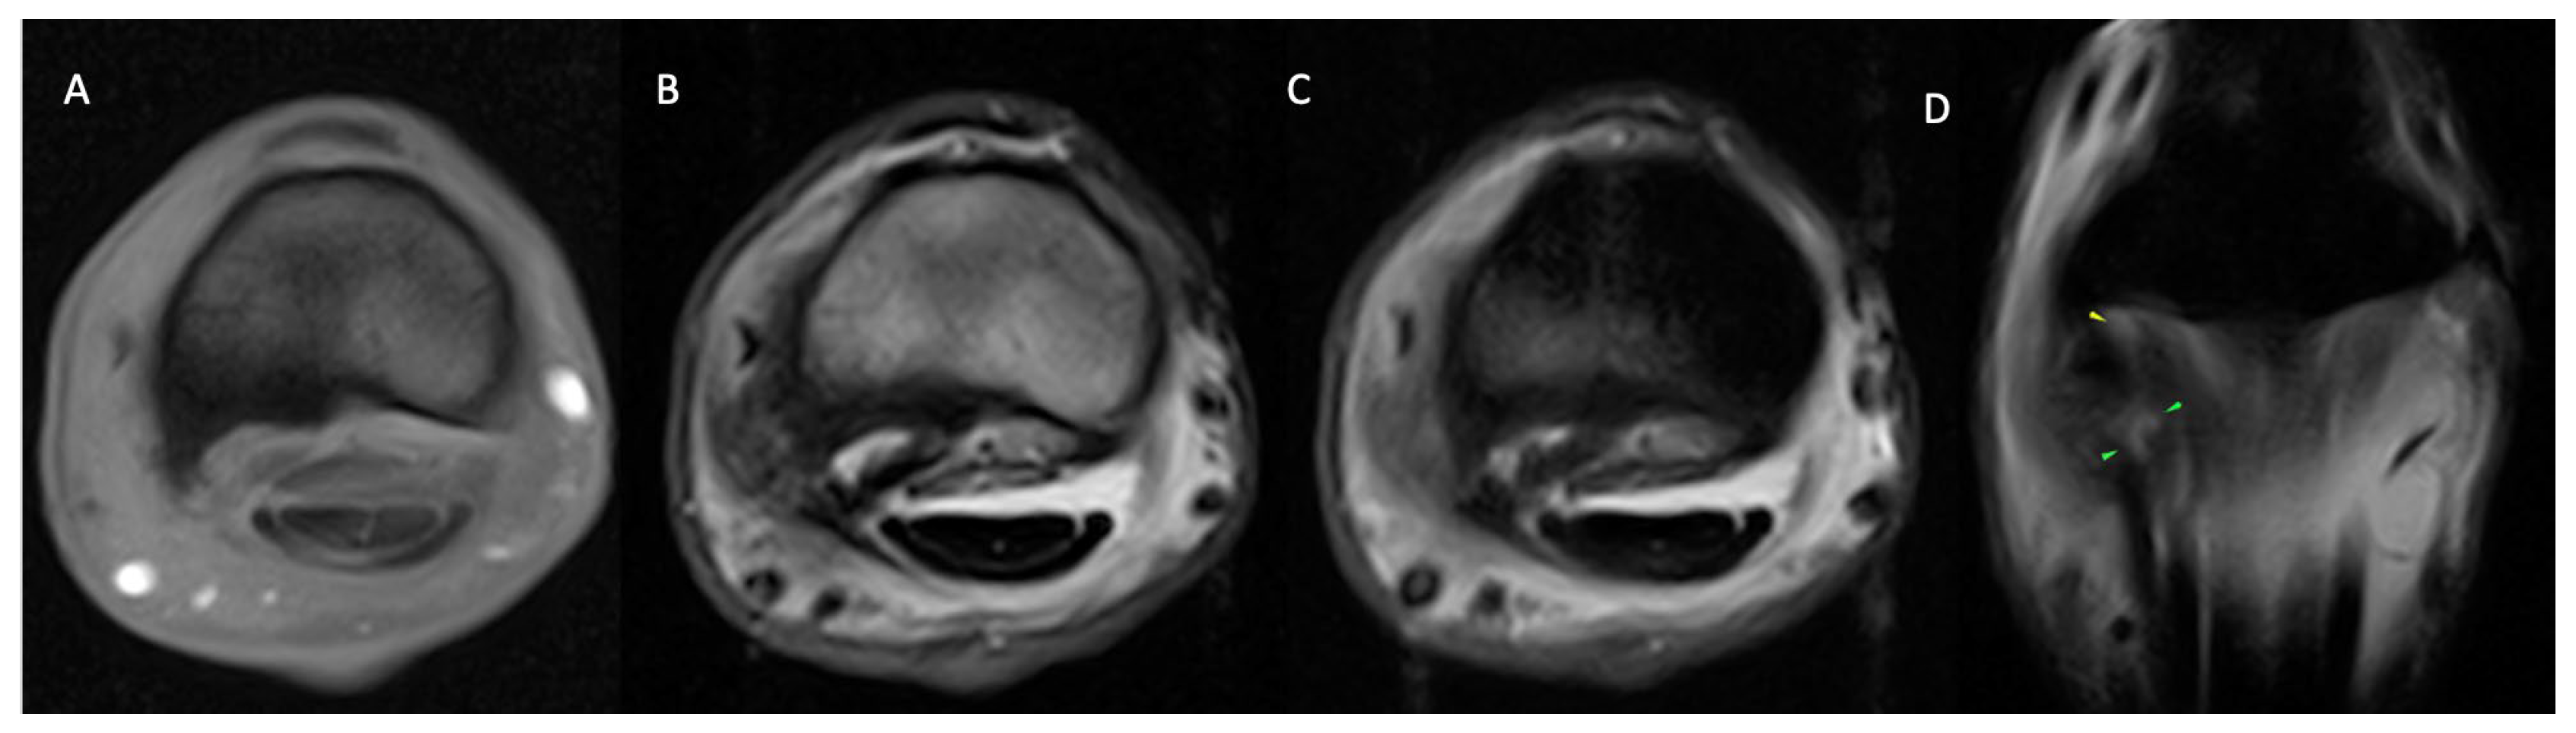

3.2.1. Osseous Pathology

3.2.2. Joint Pathology

3.2.3. Soft Tissue Pathology